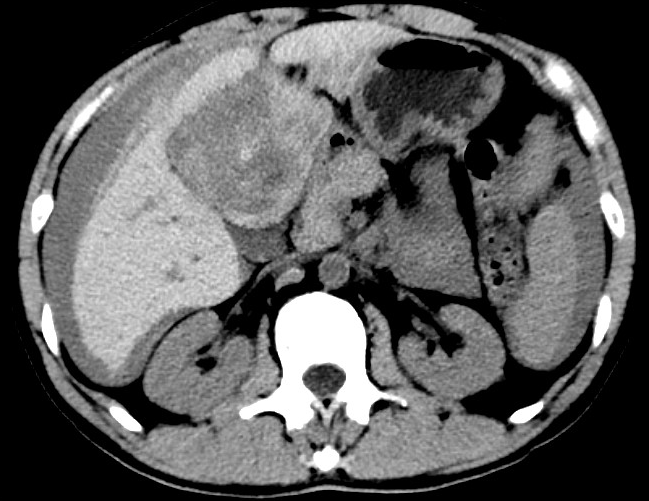

放下電話(huà)的白葦急赴消內(nèi)三搶救室會(huì)診,經(jīng)仔細(xì)查體、對(duì)患者腹部CT進(jìn)行詳細(xì)閱片、綜合評(píng)估患者后,考慮患者是肝占位破裂出血。患者病情十分緊急、一刻也不容耽誤,需立刻急診行肝動(dòng)脈造影 栓塞術(shù)進(jìn)行止血治療,在與患者家屬溝通后,立即通知消化介入室準(zhǔn)備急診手術(shù)。

入手術(shù)室時(shí),患者神志迷糊,口唇干燥、重度貧血貌,心電監(jiān)護(hù)提示:心率140-160次/分,血壓70/43mmHg,這是失血性休克的表現(xiàn)!白葦快速建立靜脈通道緊急給予輸血,升壓,止血等液,立即給予肝動(dòng)脈造影,術(shù)中發(fā)現(xiàn)肝左葉疑似腫瘤病灶、病灶周?chē)芊种в性煊皠┩庖?,考慮血管破裂出血,迅速給予栓塞微球進(jìn)行肝動(dòng)脈栓塞。整個(gè)手術(shù)過(guò)程不足20分鐘,術(shù)后即刻患者心率降至100-110次/分、血壓升至90/60mmHg。

術(shù)后給予積極抗炎,止血,保肝、利尿等對(duì)癥治療,復(fù)查血常規(guī)提示活動(dòng)性出血停止后,在超聲引導(dǎo)下行腹腔穿刺引流術(shù),術(shù)后3天共引流出血性腹水約4000ml。患者經(jīng)復(fù)查各項(xiàng)指標(biāo)均趨于正常,復(fù)查CT提示腹腔積血已基本吸收,患者康復(fù)出院。